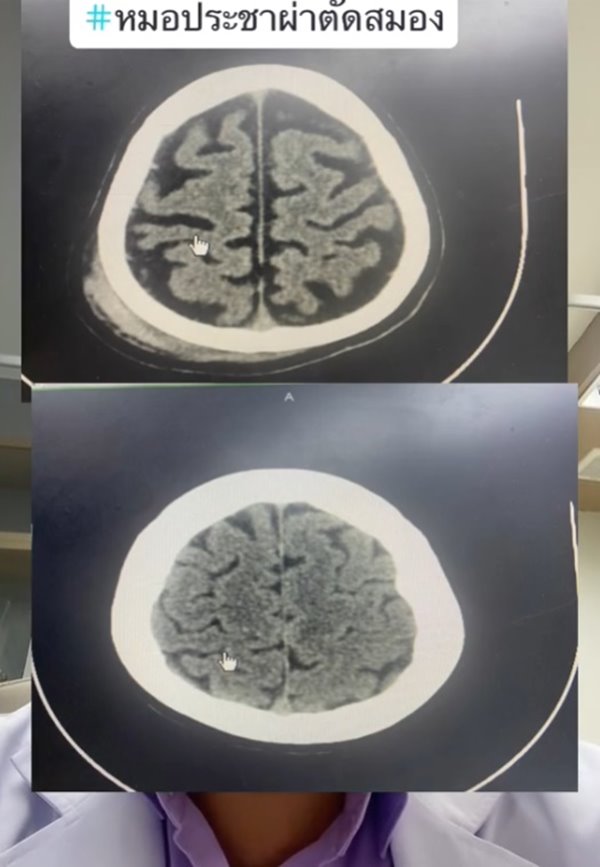

เปิดภาพเทียบให้ดูชัด ๆ สมองคนทั่วไปกับคนติดเหล้า เห็นภาพซีทีสแกนชัดเจน พบคนกินเหล้าจะมีอาการสมองฝ่อ ล้มนิดเดียวเลือดออกในสมอง ต่างกับคนทั่วไปชัดเจน ใครกินเหล้าต้องคิดให้ดี

เราอาจจะรู้กันว่า การติดเหล้านั้นมีผลทำให้เป็นโรคตับแข็ง และเป็นปัจจัยที่ทำให้เกิดโรคร้ายต่าง ๆ ตามมาได้มาก แต่ในความเป็นจริงแล้ว การดื่มเหล้าและมีอาการติดเหล้า ก็ส่งผลต่อสมองได้เช่นกัน และล่าสุดก็มีภาพซีทีสแกนมายืนยันในเรื่องนี้แล้ว

วันที่ 30 กรกฎาคม 2566 TikTok @doctor.pracha_neuro_surg ของ นพ.ประชา กัญญาประสิทธิ์ ประสาทศัลยแพทย์ มีการเล่าเรื่องราวประสบการณ์การผ่าตัดสมอง พร้อมข้อเตือนใจประชาชน โดยเปรียบเทียบกันระหว่าง สมองคนทั่วไปกับสมองคนที่ติดเหล้า มันต่างกันอย่างไรบ้าง คลิปนี้มีคนดูมากกว่า 1 ล้านครั้ง

หมอประชายังเล่าเพิ่มเติมว่า คนที่ดื่มเหล้าบ่อย ๆ เวลาล้มหัวกระแทก จะทำให้เลือดออกได้ง่าย เพราะเนื้อที่สมองน้อย ผลกระทบอื่น ๆ ก็ยังมีโอกาสเป็นเบาหวาน ไขมัน โอกาสอัมพาตจากสโตรก ดังนั้น มีโอกาสเสียชีวิตหรือพิการมากกว่าคนทั่วไป